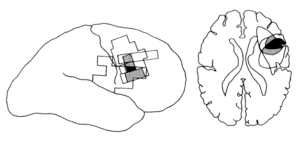

この5名に共通する損傷領域として下前頭回の一部であるブロードマン44野(左半球の言語領域であるブローカ野の右半球相同部位)が共通していること、

また多くの場合その直下の白質繊維にも損傷が見られていたこと、

右前頭葉の限局性梗塞後に左側の視力喪失を示す5人の患者が提示される。 病変の位置は、コンピュータ断層撮影法または磁気共鳴画像法を用いて評価した。 病変重複の一般的な領域は小さく、下前頭回の背側面(Brodmannの領域44)とそのすぐ下にある白質に限られていた。 この皮質領域は右半球のBrocaの領域の相同部位の一部であり、人間の運動前野の一部であると考えられている。 この領域に対する損傷の無視との関連は、それが視覚空間における注意を向けるのに重要な役割を果たす可能性があることを示唆している。